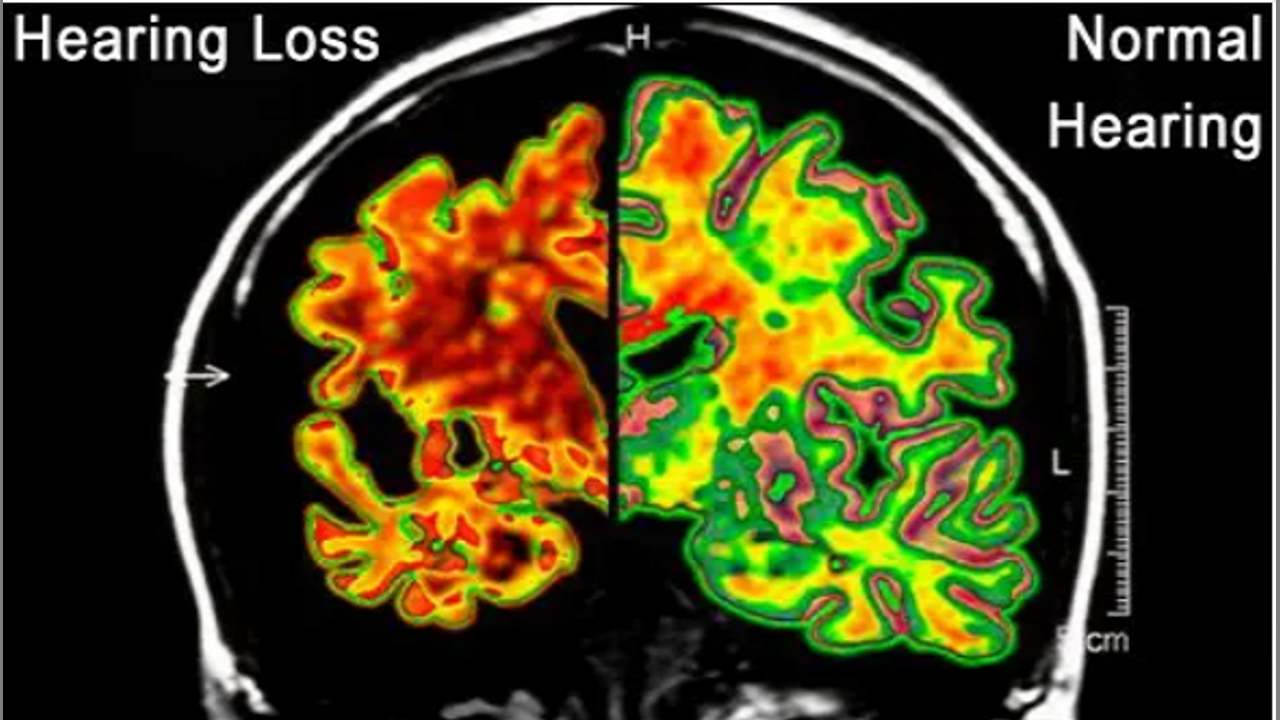

Untreated Hearing Loss and Cognitive Decline